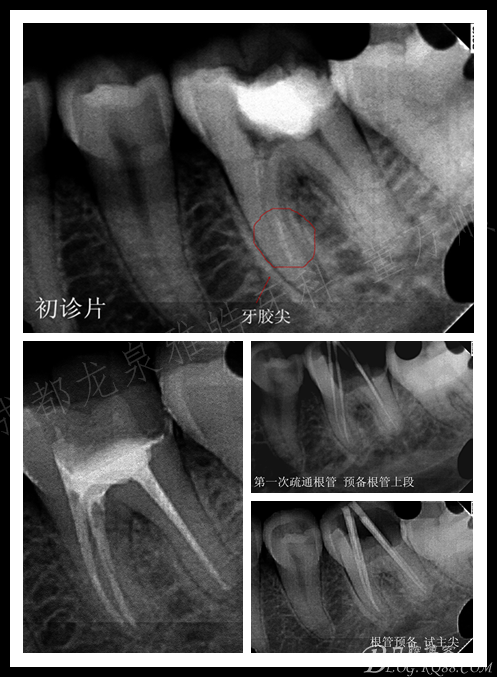

龋坏面积非常大 患者是在日本留学的时候做的治疗,由于当时没有及时的复诊导致现在的情况 ,患牙有明显的自发痛症状,阵发性钝痛。

超声器械对远中稍加施力即可看到根管口,8号挫探查根管虽说阻力很大,但还是有下去的趋势。

近中就麻烦了 怎么也探查不到根管口。 操作时间长了 ,索性预约下次处理。

复诊非常准时 ,超声配合牙片 定位根管的大致走向,一点一点的往下走,很快 近舌根管口找到了,8号挫慢慢平衡立法下至中段。窃喜

近中 由于个人操作问题 差点搞个人造根管出来,近颊根是耗时最久的 还好后来没有造成更严重的后果,期间配合超声荡洗,行根管预备 充填

复查虽然术后反应消失了,但是 根管并没有做到标准的工作长度。相信我,我真的已经尽力了。